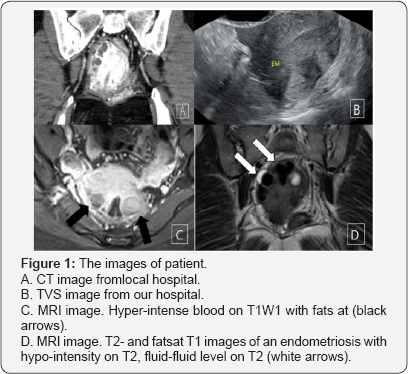

Three month ago the patient visited local hospital due to abnormal uterine bleeding (AUB) and underwent dilation and curettage (D&C). After D&C, she took oral contraceptives (OCs) for control AUB. During OCs medication, severe pain was occurred and she was admitted to the hospital. The laboratory finding shows elevated C-reactive protein (CRP), leukocytosis, and contrast-enhanced CT scan of the chest and abdomen revealed enteritis, and inflammatory lesions and leiomyoma with secondary degeneration in posterior wall of uterus (Figure 1A). The size of leiomyomas was up to 4.3cm. Antibiotics and non-steroid anti-inflammatory drug (NSAID) were administered. However, pelvic pain was not improved and she was transferred to our hospital.

Transvaginal ultrasound (TVS) showed multiple hypoechoic lesions in the posterior surface of uterus (Figure 1B). Despite the use of antibiotics, symptom did not improve. So Contrast- enhanced magnetic resonance image (MRI) of the pelvis was checked and radiologist reported an endometriosis involving uterus with combined infection (Figure 1C & 1D).

Characteristic finding of endometrioma for MRI is increased signal intensity on T1-weighted images and decreased signal on T2-weighted images, sometimes referred to as “shading”. MRI has a greater than 90% sensitivity and specificity for endometrioma [6]. CT does not use for diagnosis of endometriosis due to lack both sensitivity and specificity, and a variety of nonspecific radiologic findings may be seen [7].